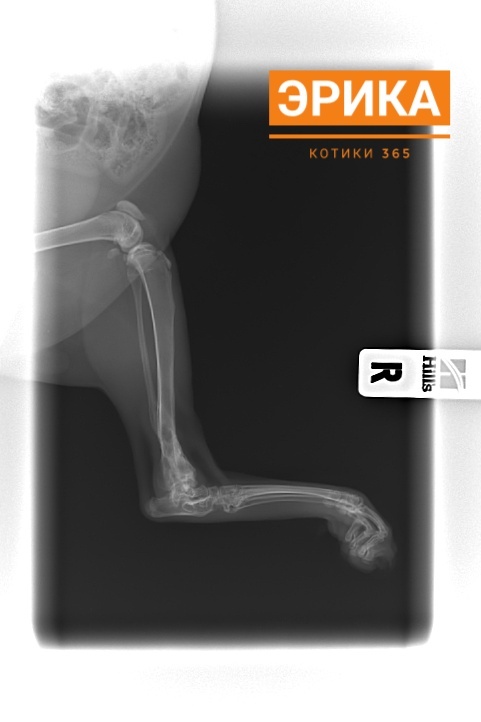

Эрика 16.12.2025

Сегодня Эрика была в клинике на снятии швов и сделала рентген.

По рентгену все срослось хорошо.

"У скакательного сустава восстановлена полная амплитуда движений без ограничений ".

Результат превзошёл ожидания и прогнозы.

Эрика теперь может прыгать и бегать, как будто никакого перелома и не было.